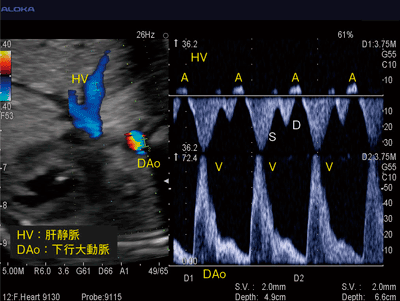

また,成人の心エコー検査のみならず,胎児心疾患の診断にも応用されることが期待されている。このうち,胎児不整脈の症例を提示する。胎児不整脈は1〜2%の妊娠で認められる,比較的よく遭遇する疾患である。治療を必要としない場合が多いが,胎児水腫や胎児死亡を引き起こすことがあるため,正確な診断や管理が必要となる。胎児では,心電図をとることが難しいため,さまざまな方法により診断が行われている。その中で,Dual Dopplerを用いて,肝静脈と下行大動脈の同時血流計測(HV-DAo法)という新しい診断方法も報告されている(図5)。肝静脈血流には,S波,D波に引き続き,心房収縮による逆流波A波を認め,下行大動脈血流には心室収縮によるV波が表示される。したがって,得られたA波同士,V波同士およびA波とV波の間隔から,胎児不整脈を評価できる。従来の1方向のドプラ法では,静脈血流と動脈血流が重なるケースにおいて,A波とV波の分離が難しかったが,別々に表示できることにより,心房収縮と心室収縮の関係や,それぞれのリズムを理解しやすいといった利点が挙げられる。

図5 Dual Dopplerによる胎児不整脈の診断

(画像ご提供:徳島大学病院産婦人科・加地 剛先生)